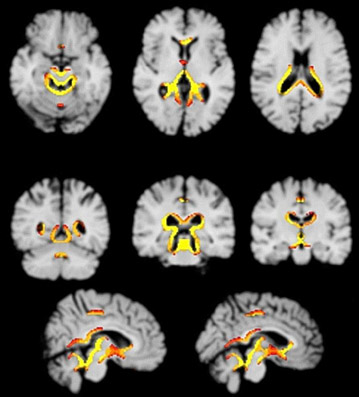

MR-Schnitte durch das Gehirn einer 49jährigen Frau, die seit zehn Jahren alkoholabhängig war, beim Beginn ihrer Behandlung. Die alkoholbedingte Hirnschrumpfung ist an erweiterten Hirnwasserkammern und -furchen erkennbar. Mit der Abstinenz gewann das Gehirn der Patientin rund drei Prozent an Volumen. Farbig hervorgehoben sind die Bereiche, in denen bei der Mehrzahl der 15 untersuchten Patienten eine derartige Hirnregeneration beobachtet wurde. Abbildung: Andreas Bartsch/Georg Homola